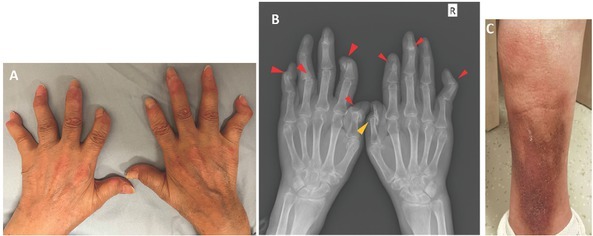

We report a case of a 68-year-old woman with chronic and severely destructive arthritis for 8 years with imaging features mimicking psoriatic arthritis (PsA) but serological evidence of systemic lupus erythematosus. Both the lupus panniculitis-like rash and the presence of interstitial lung disease were considered manifestations of systemic involvement of SLE.

我们报告了一例68岁女性患者的病例,她患有慢性严重破坏性关节炎8年,影像学特征类似银屑病关节炎(PsA),但血清学证据显示她患有系统性红斑狼疮。狼疮泛发性皮疹和间质性肺病都被认为是系统性红斑狼疮全身受累的表现。